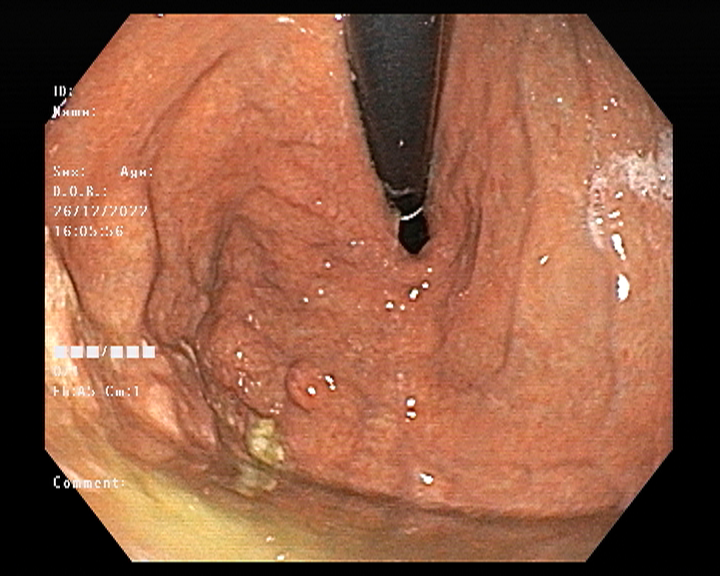

Endoscopy and colonoscopy are safe and accurate procedures used to directly examine the digestive tract and detect the root cause of chronic acidity, GERD, abdominal pain, bleeding, and bowel irregularities. These minimally invasive tests help identify ulcers, inflammation, infections, polyps, strictures, and early cancerous changes.

At Sapphire Gastroenterology Center, modern endoscopic equipment ensures precise diagnosis and, when required, therapeutic intervention during the same procedure. Based on findings, targeted treatment plans are created, including medication, diet guidance, and preventive strategies. Early diagnosis through endoscopy and colonoscopy plays a crucial role in preventing serious complications and improving long-term digestive health.